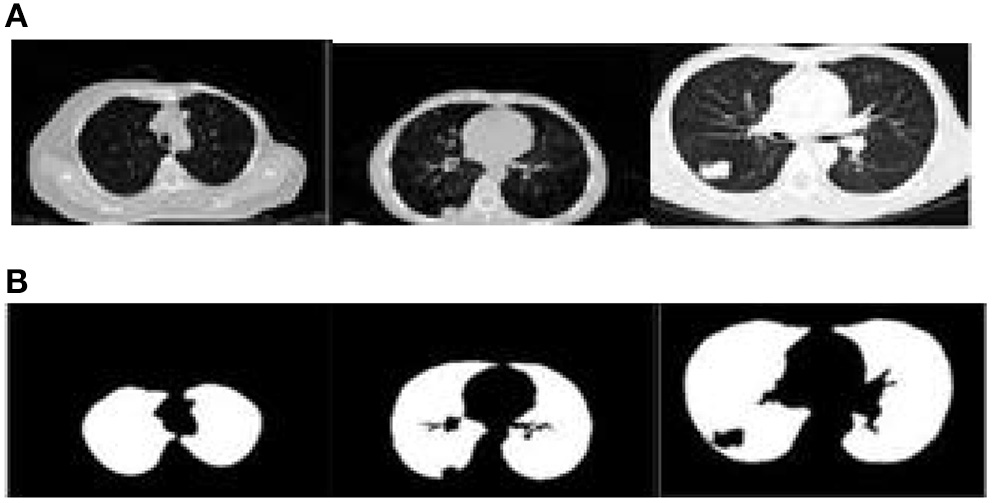

The proposed algorithm is used to segment the 3D multimodal medical images in the test set. Five brain images in the DeepLesion data set and three lung images in the SCR data set are selected for this study and the comparison of the effect pre- and postsegmentation is shown in Figures 2, 3.

Figure 3

Comparison of the effect of lung image segmentation before and after. (A) Presegmentation lung images. (B) Lung images postsegmentation by proposed algorithm.

According to Figures 2, 3, the application of the segmentation proposed algorithm can effectively achieve medical image segmentation. The image edge is clear for postsegmentation, the noise points can be effectively removed, and the definition is high.